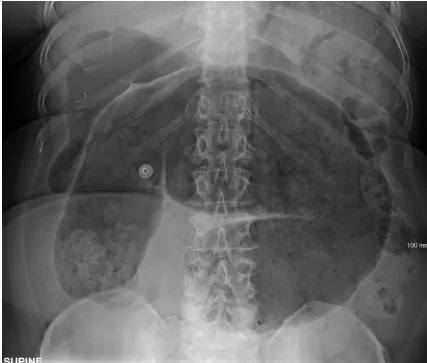

- Toxic megacolon: Colon diameter >6cm on AXR

✓ Toxic megacolon: Colon >6cm on AXR; medical emergency requiring urgent surgical review